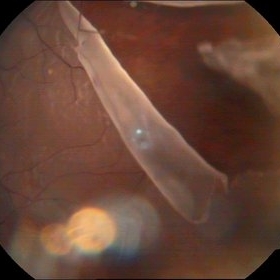

Rerinal Detachment with PVR

Sep 10 2014 by Mehul A Shah

A myopic male patient 35-years-old presented to outdoor and found to have retinal detachment with multiple fixed folds.

Photographer: Drashti Netralaya,Dahod

Imaging device: FF 450

Condition/keywords: proliferative vitreoretinopathy (PVR)